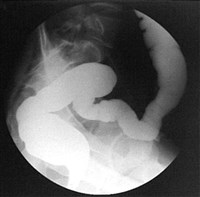

Исследование начинается с ориентировочной рентгеноскопии кишки (осмотра на экране), которая проводится до введения контрастной массы. При этом обращается внимание на повышенное газосодержание в кишечнике, характер расположения газовых пузырей. Далее просвет толстой кишки заполняют контрастным веществом (контрастная клизма). При этом появляется возможность установить тонкие морфологические изменения стенок толстой кишки, в особенности, если одновременно производится также изучение рельефа слизистой кишки.

При введении контраста необходимо следить за расправлением кишки, состоянием ее контуров, продвижением контрастной массы и ее задержкой. Найденные при рентгеноскопии патологические изменения подлежат рентгенографии (снимки). Осмотр продолжается до тех пор, пока контрастная масса не достигнет слепой кишки и не заполнит ее. После того, как достигнуто заполнение всей толстой кишки, производится один обзорный снимок. Затем больному предлагается опорожнить содержимое кишки, после чего его снова подвергают рентгеноскопии. При этом обращают внимание на то, в каком количестве и в каких отделах толстой кишки задержалась контрастная масса. При определенных заболеваниях пораженные отрезки толстой кишки опорожняют свое содержимое быстрее и совершеннее, чем здоровые участки. Если на каком-нибудь участке имеется сужение, то контрастная масса задерживается выше этого места, тогда как отдел кишки, расположенный ниже, оказывается свободным от содержимого. После опорожнения толстой кишки хорошо визуализируется рельеф слизистой.

Помимо описанного, существует способ исследования толстой кишки при помощи комбинированного введения контрастной массы и воздуха. При этом вначале вводится контрастная взвесь, затем больному предлагается частично опорожнить кишечник, после чего под контролем экрана рентгеноскопа производится медленное, с короткими интервалами, раздувание толстой кишки воздухом. При таком способе исследования лучше визуализируется рельеф слизистой кишки.